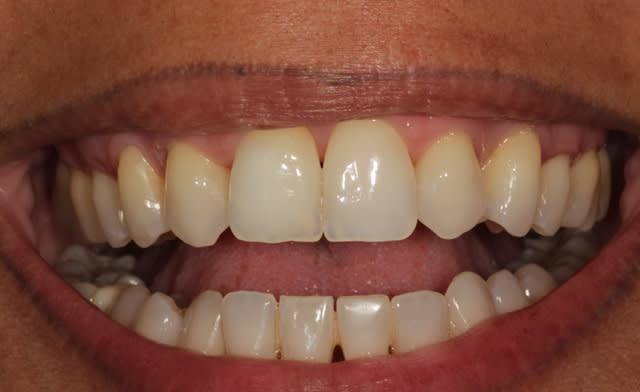

image 1: pansement composite avant endo

image 2: combo strat. après endo tout en Gaenial: A2/A1/TE/JE et tescera blanc. Photo prise à 7 jours. Patient moyennement satisfait.